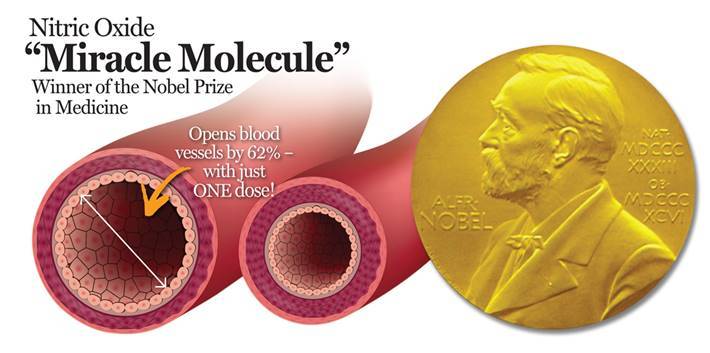

Immune system booster - NITRIC OXIDE 2400 Mg - 3B - repairing of blood vessels